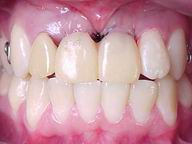

| Antes: Prótese removível provisória, conforme se apresentou à primeira consulta |

Depois: Próteses cerâmicas ao final do tratamento |